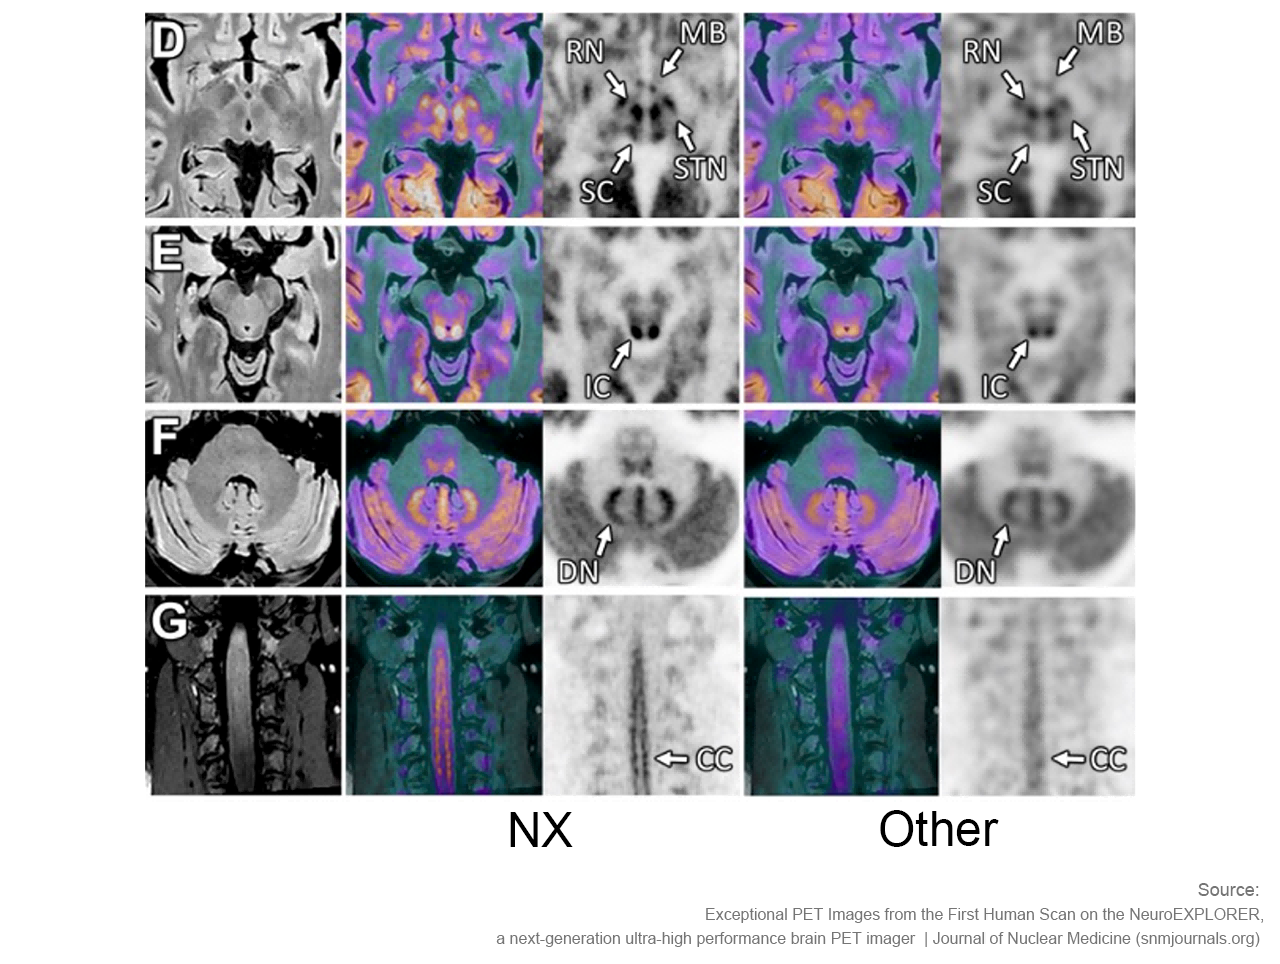

NeuroExplorer (NX)产出的脑部影像图

超高灵敏度 重置探索边界

NeuroExplorer拥有基于NEMA NU 2-2018标准的超高灵敏度:46cps/kBq,同时配备着先进的时间飞行技术,进一步增强了NX的综合性能。

卓越空间分辨率 洞察大脑微观

小型探测器元件确保最精微的结构能被检测,甚至探查特定脑核中的神经递质运动。搭载1.5mm的有效空间分辨率,带来前所未见的解剖细节。

NeuroExplorer (NX)产出的脑部影像图与其他设备产出的脑部影像图对比

“从我们目前获取的图像来看,使用NeuroExplorer扫出的图像是世界上最好的,因此我们能够真正做到更好地缩小范围,聚焦更小的信号,观察大脑更为微末的区域,这为我们打开了新的窗口,去‘见所未见’。”Carson教授对NX的诞生和即将围绕其展开的一系列研究满怀期待,“有了NeuroExplorer这样强大的设备,我们步履不停,也正将迎来一个重要的突破,那就是和制药行业的合作。”